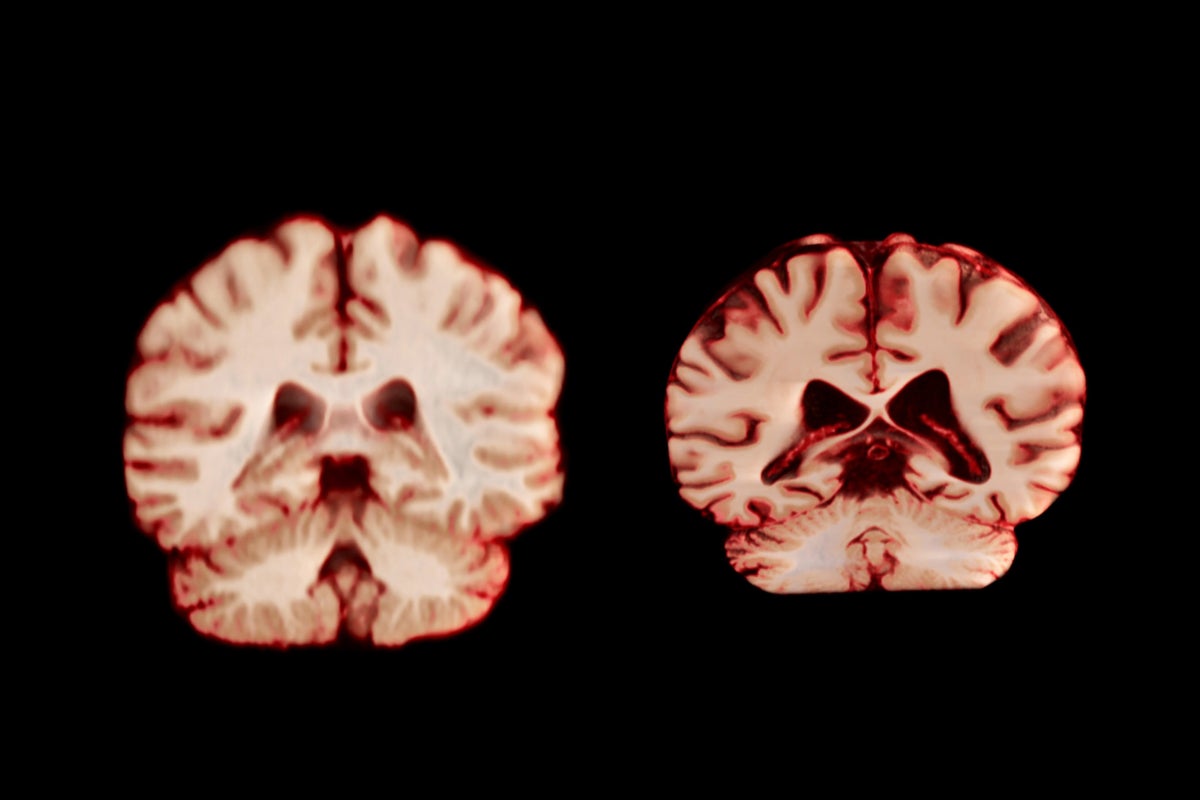

A healthy brain (left) and a brain affected by Alzheimer’s disease.

During ageing, men experience a greater reduction in volume across more regions of the brain than women do, according to a longitudinal study published today in the Proceedings of the National Academy of Sciences. The authors suggest this means that age-related brain changes do not explain why women are more frequently diagnosed with Alzheimer’s disease than men are.

Nearly twice as many women are diagnosed with Alzheimer’s disease as men, and ageing is the biggest risk factor for the disease. This has prompted research into age-related sex differences in the brain. “If women’s brains declined more, that could have helped explain their higher Alzheimer’s prevalence,” says co-author Anne Ravndal, a PhD student at the University of Oslo.